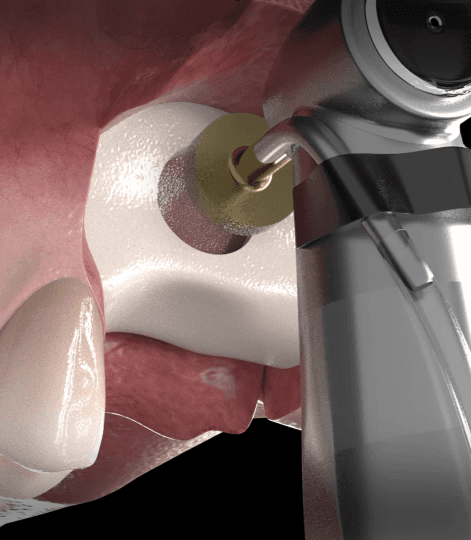

03

이식한 뼈 위에 차폐막을 덮어 고정

차폐막은 이식한 뼈 위를 덮어 외부 자극이나 잇몸세포 침입을 막고, 뼈가 제대로 자랄 수 있도록 안정된 환경을 만들어줍니다.